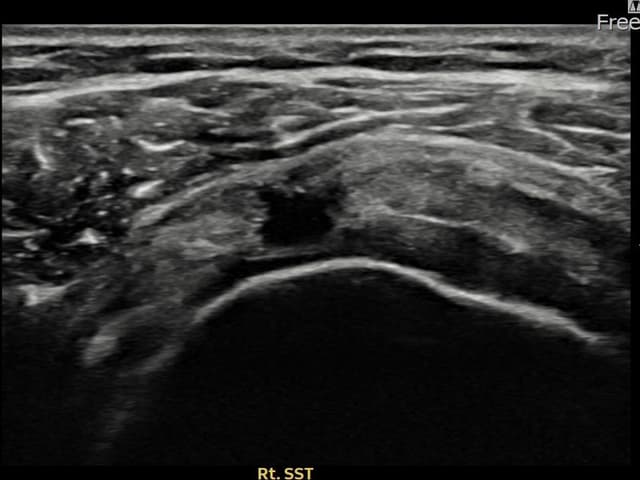

[촬영시기:24.09.23~24.12.03]

[어깨인대 축소봉합술] 우측 어깨 통증과 팔 들어올리기 제한으로 내원하셨습니다.